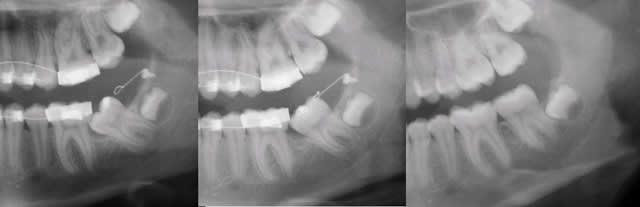

Chacun interprète en fonction de la manière dont il imagine que c'est en bouche (niveau de l'émergence de la ligature, hauteur de la gencive..).

Calou, pourrais-tu montrer une photo, que l'on puisse se mettre d'accord ?

Le plus simple est d'en utiliser une courte qu'on placera dans le bord antérieur de la branche montante après l'avoir enfilée dans l'anneau d'une ligature qui émergera, elle, en distal de la molaire. Voir planche photo jointe.